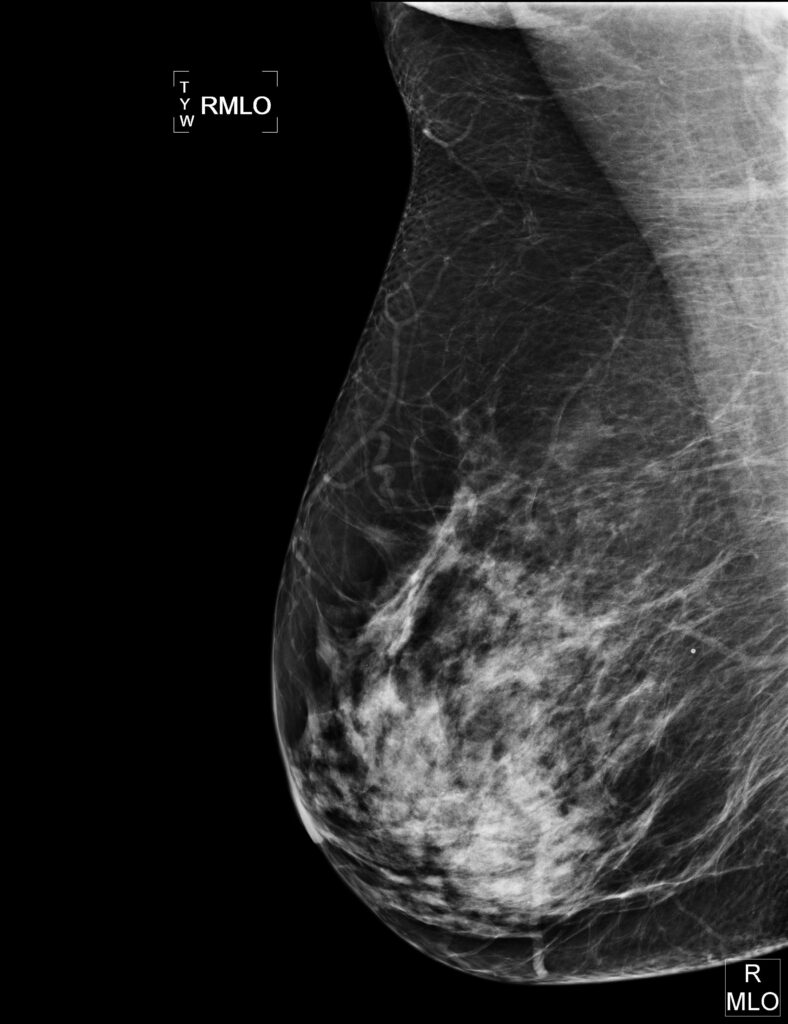

Tumori al seno: lo screening continua a salvare molte vite, ma un tumore su tre è innocuo

Anche se gli screening al seno sono ancora l’arma migliore per individuare il cancro allo stadio iniziale e continuino a salvare migliaia di vite ogni anno circa un terzo delle forme tumorali diagnosticate potrebbero in realta’ essere innocue. E’ quanto e’ emerso da uno studio condotto in cinque Paesi, tra cui il Regno Unito, secondo il quale alcune donne vengono operate o trattate con chemioterapia inutilmente per forme tumorali che difficilmente potrebbero svilupparsi e minacciare effettivamente la loro vita.

La ricerca, scrive il sito web della Bbc, e’ stata pubblicata dal British Medical Journal (Bmj) ma e’ stata contestata dalle organizzazioni che difendono il sistema dei test e delle diagnosi precoci come unico sistema per salvare la vita delle pazienti. Anche perche’ con gli attuali mezzi a disposizione non e’ possibile accertare se i tumori individuati siano forme letali o meno. Ma i ricercatori del Nordic Cochrane Centre in Danimarca sostengono che i risultati del loro studio dimostrano che gli screening del seno possono in qualche caso condurre a casi di “sovra-diagnosi”.

“I test possono portare alla scoperta precoce di un cancro letale ma possono anche individuarne uno innocuo che non causera’ danni o sintomi”, sostengono i medici danesi sul Bmj, Sulla stessa linea il professore Gilbert Welch del Darthmouyh Institute for Helth Policy: le mammografie “danno l’opportunita’ di aiutare alcune donne ma possono anche avere la conseguenza di portare altre ad essere sottoposte ai trattamenti per il tumore (al senso) senza necessita’ anche perche’non si tratta di interventi leggeri”. Di parere nettamente opposto la professoressa Julietta Patnick, direttore proprio del Programma di screening per i tumori del Servizio Sanitario Nazionale britannico secondo cui “una donna su otto sarebbe morta senza il test”.

Secondo le sue stime nella sola Inghilterra le mammografie salvano 1.400 vite ogni anno. Per questo ha rinnovato l’appello a test il piu’ precoci possibili. Concorda con lei Sara Cant del Breaktrough Breast Cancer. Anzi la dottoressa si augura che lo studio non scoraggi le donne a sottoporsi all’analisi: “Sfortunatamente al momento non e’ possibile predire quali tumori individuati attraversi i test si svilupperanno in forme aggressive e quali cresceranno molto lentamente. Ma basandoci sui nostri dati al momento pensiamo che i benefici della scoperta precoce siano ancora maggiori dei rischi”. Basta ricordare, ha concluso, che “nel Regno Unito ancora 12.000 donne muoiono ogni anno di cancro al seno”.